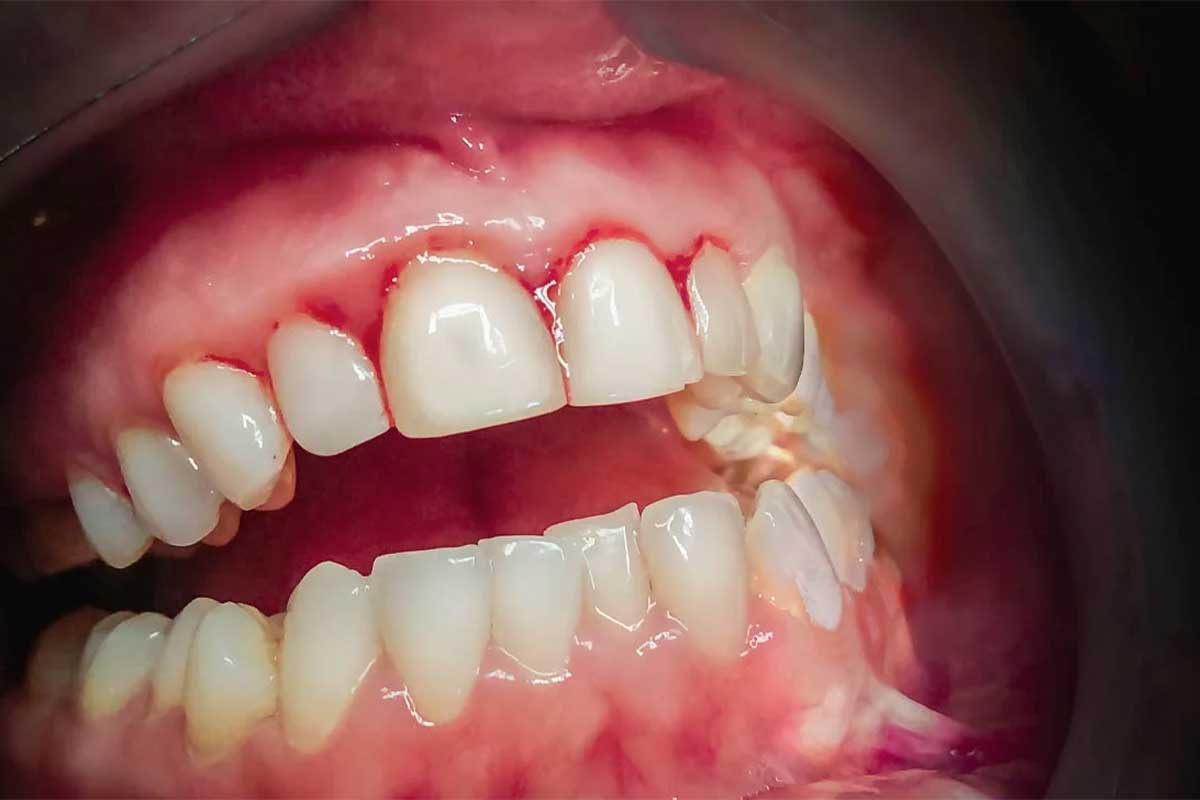

یکی از بیماریهای شایع این بافت مهم عفونت لثه است که شاید دندانپزشک آن را بیماری پریودنتال یا پریودنتیت بنامد. درمان نشدن بیماری لثه میتواند باعث تورم، قرمزی، درد و از دست دادن دندان شود. التهاب لثه یا به قول دنداپزشکان ژنژیویت، باعث تورم، قرمزی و خونریزی در قسمتی از لثه میشود که با دندانها در تماس است و آنها را نگه میدارد. این وضعیت یک نوع خفیفتر از بیماری لثه است که اگر درمان نشود ممکن است به عفونت لثه منجر شود.

در مرحلهی ابتدایی احتمالا لثهها قرمز میشوند که این تغییر رنگ با تورم همراه است. لثهها ممکن است موقع مسواک زدن خونریزی داشته باشند اما دندانها هنوز سر جایشان هستند. بیماری لثه در این مرحله درمان شدنی است و بافت آن به وضعیت قبل برمیگردد.

باکتریها لثه و استخوانها را از بین میبرند، همان بخشهایی که دندانها را سر جایشان محکم نگه میدارند. احتمالا لثهها تغییر شکل میدهند و مشکل پیدا میکنند، مثلا خونریزی زیاد. ممکن است چرکی در امتداد خط لثه ببینید که نشانهی عفونت است.

- خونریزی لثهها حین مسواک زدن

- خونریزی لثه شبها و در طول خواب

- خونریزی لثه بر اثر خوردن مواد غذایی سفت

- لثههای قرمز و متورم (لثه سالم باید صورتی و سفت باشد)